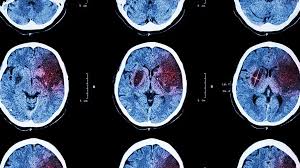

Explorer les avantages de la pratique de la respiration unilatérale des narines après un AVC

Explorer les avantages de la pratique de la respiration unilatérale des narines après un AVC : attention, langage, capacités spatiales, dépression et anxiété Rebecca Shisler …